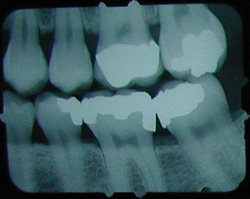

No cavity on first X-ray.

Months later, cavities that start

between the teeth can't be seen by visual examination,

but they can be detected on an X-ray.

This cavity was detected and filled before the patient felt any discomfort, and before the nerve became infected or the tooth became abscessed.

There is another cavity shown in the X-ray on the right. Can you find it? It's difficult for the untrained eye to spot. Click here to see where it is. (Hint: It's not the left edge of the top left tooth. That's just the edge of the frame around the X-ray).